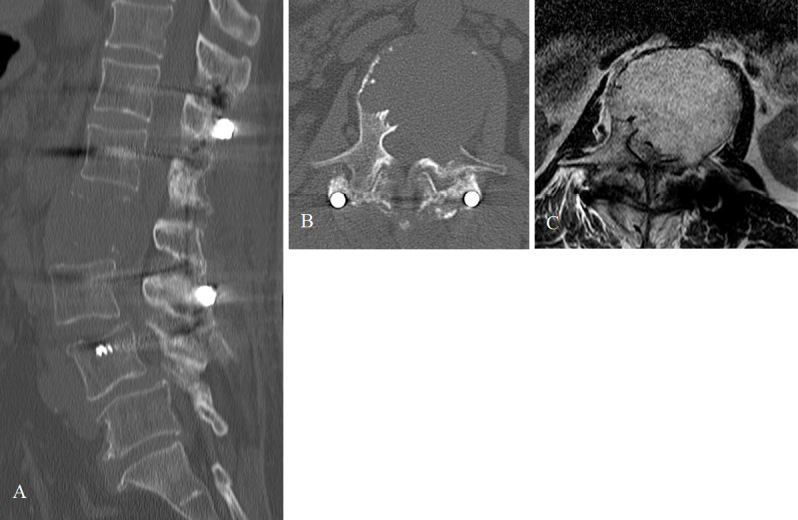

Abstract Image